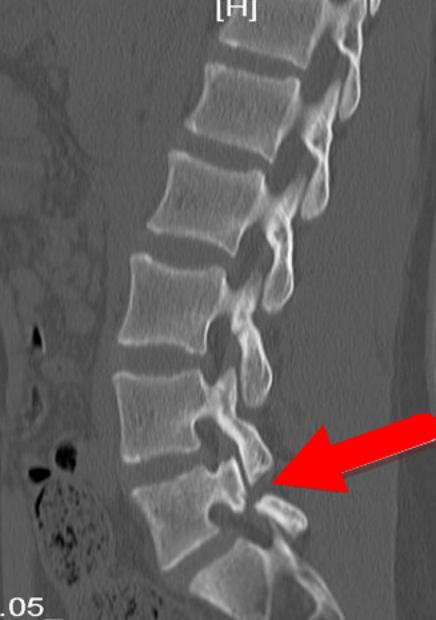

人体中,脊椎可分为椎体、椎弓、椎板、上下关节突、横突与棘突。上下关节突之间较为狭小的部分就是椎弓根峡部。如下图所示,就是腰L3和腰4之间的峡部。

峡部最重要的作用就是防止椎体向前滑移。